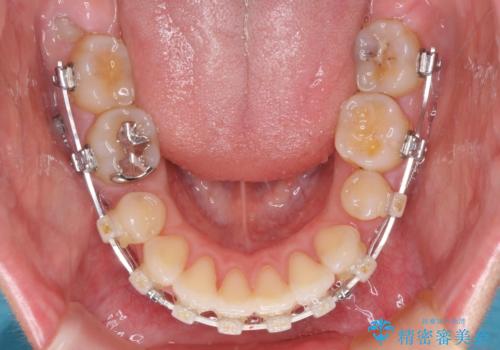

- 矯正装置

- 審美装置

上下正中を左右対称に揃えるため、アンカースクリューや補助装置を使用しながら口元を下げていくこととしました。